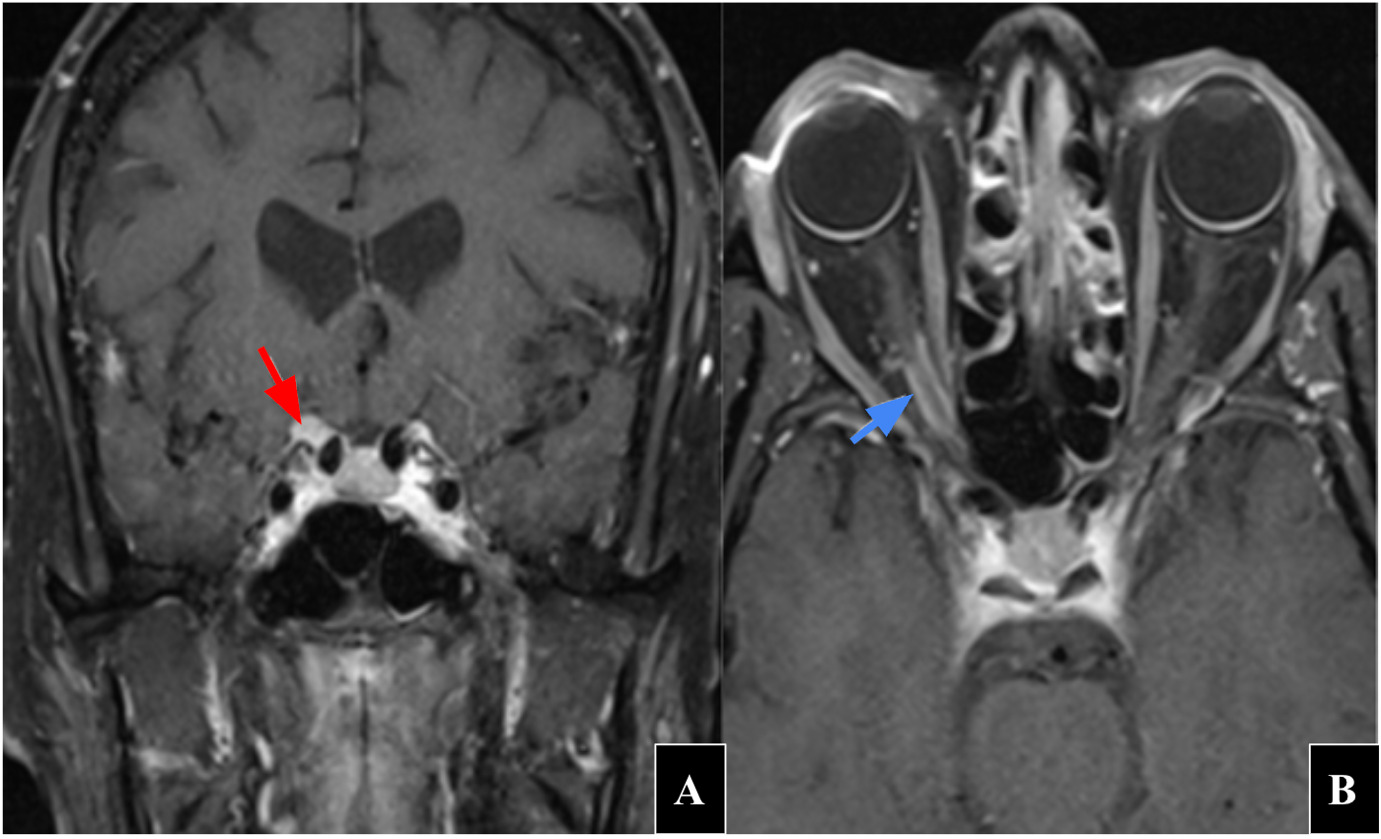

Figure 3 shows optical coherence tomography of the optic nerve which revealed small optic discs bilaterally. The right eye showed nasal retinal nerve fiber layer elevation while the left eye demonstrated inferior retinal nerve fiber layer elevation. Vitreopapillary traction was present in both eyes. Figure 4 shows optical coherence tomography of the macula and ganglion cell complex which showed diffuse thinning 360 degrees in the right eye while the left eye was within normal limits.

At her initial follow-up, 1-month postoperative, visual acuity had improved to 20/60 in the right eye and remained 20/25 in the left eye. Pupillary testing showed that her pupils were equal, round, and reactive to light in both eyes with a 1.5 log unit relative afferent pupillary defect persisting in the right eye. Postoperative optical coherence tomography of the retinal nerve fiber layer demonstrated thin retinal nerve fiber layer inferior in the right eye and borderline thin temporal in the left eye with elevated areas nasal and inferior in the left eye as shown by figure 3. The ganglion cell complex was stable to initial visit as shown by figure 4. Comparison of presurgical (left) and postsurgical (right) visual field testing revealed slight improvement with persistent central scotoma but preserved peripheral vision in the right eye as shown by figure 6.

These findings were consistent with partial optic nerve recovery following decompression. Prognosis for further visual recovery is guarded due to evidence of preexisting axonal loss on optical coherence tomography and ganglion cell complex analysis.